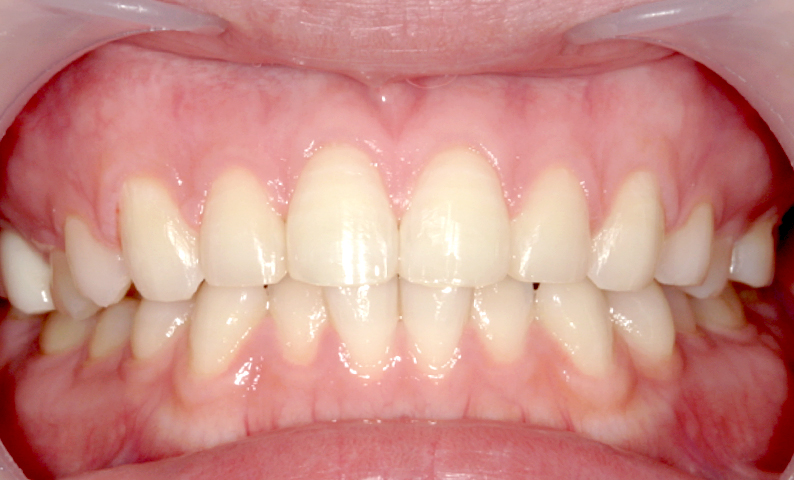

症例_013 前歯「八の字/V字型」症例

治療期間:8ヶ月金額:30万円+税20代女性八の字/V字型捻転歯上の前歯だけ